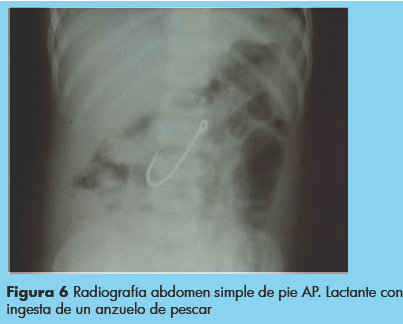

A 25/208 pacientes el cuerpo extraño fue expulsado por heces, manteniéndose hospitalizado bajo vigilancia hasta la obtención del mismo, ejemplo de ello una lactante que ingirió un anzuelo de pesca (Figuras 6 y 7).